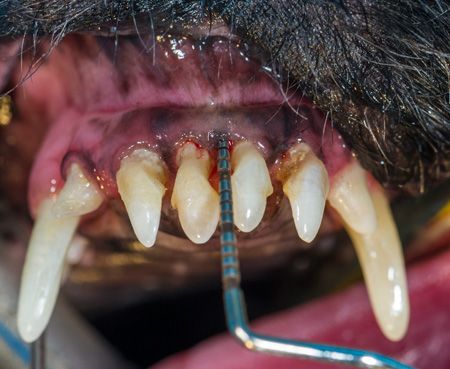

What approach would you take to fix this pups tooth and provide a solution for the long term?

Extraction isn't always the best choice for veterinary patients with tooth troubles. Find out in which cases tooth repair-not removal-can restore dental health.

When is dental extraction the treatment of choice? Find out in this first installment of a multipart series on what to do to when faced with dental pathology.